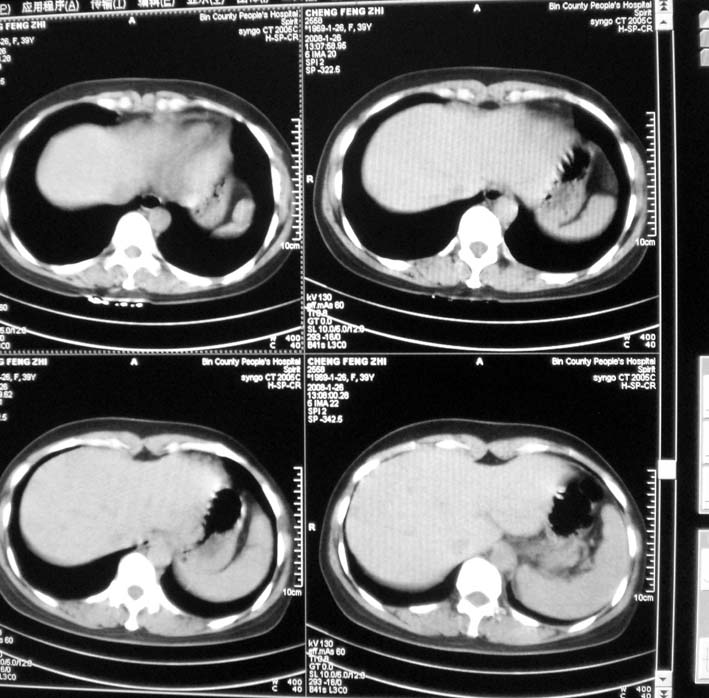

以下是引用guoke在2008-1-27 14:15:00的发言:[br]纵隔增宽,纵隔内血管境界不清,心包积液,考虑纵隔淋巴瘤.[br]

以下是引用随光逐影在2008-1-27 15:52:00的发言:[br]1)考虑为:淋巴瘤。建议:行进一步检查。2)心包积液。